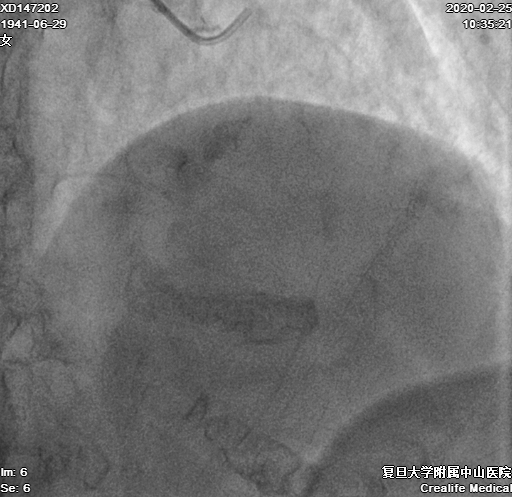

导丝通过后,Corsair微导管无法通过,在球囊辅助下尝试送入6F Guidezilla II,尝试球囊扩张右冠近段、锚定,均无法送入Guidezilla II(图6)

图6